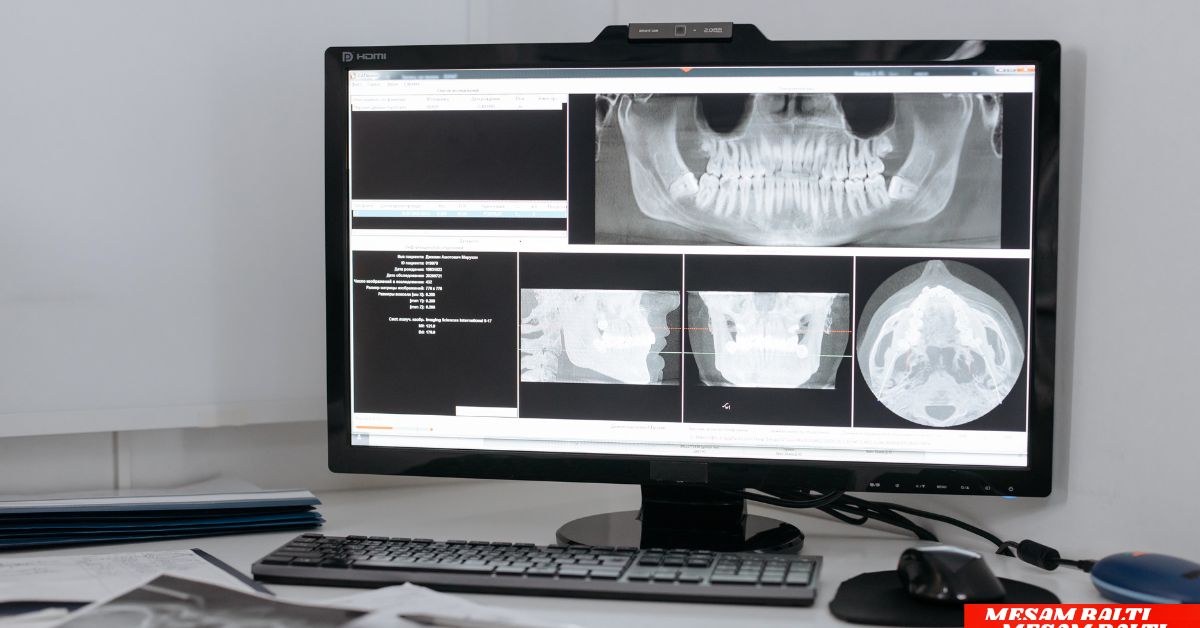

AI in radiology, for one, about how machine learning such as deep learning algorithms are being used to analyze medical images like X-rays, MRIs, CT scans, ultrasounds etc. They are trained on massive data sets of medical images to detect patterns, anomalies, and possible diagnoses that might elude the human eye.

- Image Recognition: AI for visual analysis, like convolutional neural networks (CNNs), use pixel data for identifying abnormalities, such as tumors, fractures, or infectious diseases.

- Faster Diagnoses: AI can analyze X-rays and M.R.I.s in seconds, highlighting potential problems for radiologists to examine.

- Improved Accuracy: AI cuts down on human error by spotting the subtle patterns that people overlook.